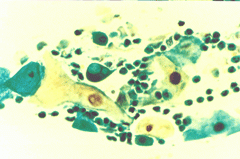

Περιστατικό ασθενούς που παρακολουθείται στο ιατρείο μας από το 1993, τότε ηλικίας 37 ετών, αρχικά λόγω ασυμπατωματικού κυτταρολογικά εμμένοντας έρπητος τραχήλου της μήτρας. Το γεγονός αυτό μας οδήγησε στην διερεύνηση της περιπτώσεως. Η ασθενής επασχε από A.I.D.S.

Είχαμε την ευκαρία να παρακολουθήσουμε ανά 6μηνο γυναικολογικά, κολποσκοιπικά και κυτταρολογικά την γυναίκα από το 1993 μεχρι και το 2008. Από τις εξετασεις αυτές, παρουσιάζουμε χαρακτηριστικές κυτταρολογικές εικόνες . Όι παρακάτω κυτταρολογικές εικονες προέρχονται από την 2η κατά σειρά εξέταση της ασθενούς το 1993. Οι κυτταρολογικές αλλοιώσεις ερπητος συνεχίζουν να υφίστανται.

Ταση γιγαντιοκυττάρωσης όλων των επιθηλιακώ στοιβάδων, κοιλοκυττάρωση, διογκωμένοι υπερχρωματικοί και ανισομεγέθεις πυρήνες , με διάλυση δομής χρωματίνης, συχνά διογκωμενοι πυρήνες με εικόνα φαινομένου ΄΄θολού γυαλιού΄΄